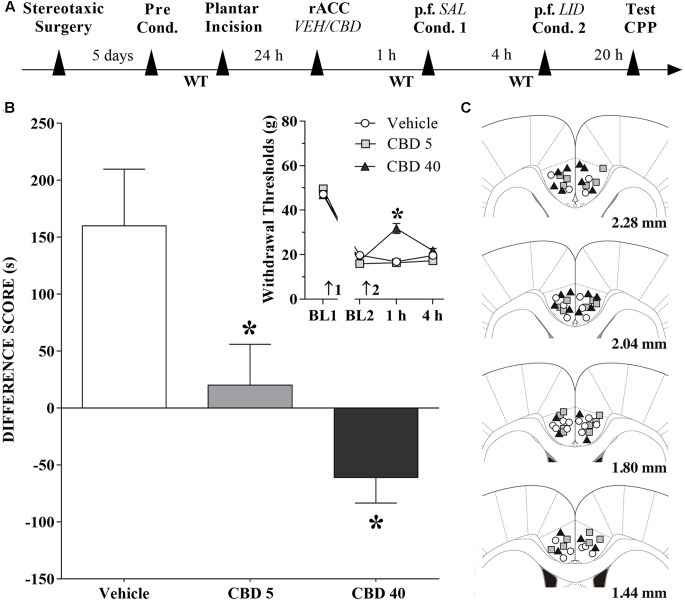

Changes Induced by CBD Injections into the rACC in the CPP Produced by Peripheral Nerve Block

A timeline of the protocol for the experiments is shown in Figure 6A. Intra-rACC injection of CBD (5 nmol/0.25 μL) reduced, and CBD (40 nmol/0.25 μL) inverted, CPP by peripheral nerve block (Figure 6B). The differences were statistically significant in terms of treatment [F(2,36) = 8.2; p < 0.01], Dunnett’s test for CBD vs vehicle in incised rats. The effects of CBD (5 and 40 nmol/0.25 μL) injected into the rACC on mechanical threshold were also evaluated. Incision pain-produced mechanical allodynia was reduced only by administration of CBD at 40 nmol/0.25 μL (insert in Figure 6B). The differences were statistically significant in terms of time [F(3,108) = 421.3; p < 0.01], treatment [F(2,36) = 10.7; p < 0.01] and interaction time × treatment [F(6,108) = 14.4; p < 0.01]. Figure 6C illustrates the microinjection sites in rACC on diagrams of cross-sections from the atlas of ref. Paxinos and Watson (2006).